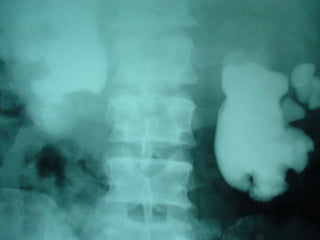

Investigations

i.v.u

19